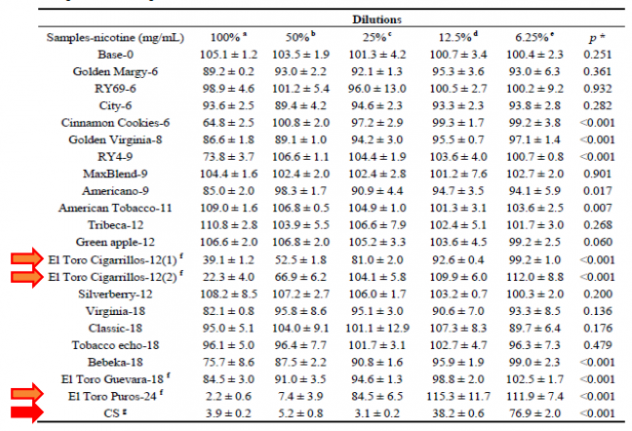

Интересные испытания были проведены в ходе токсикологических исследований, в которых изучали действие различных жидкостей на живые клетки. Интересно, что жидкости со вкусом кофе оказались наиболее неблагоприятной средой. Однако сравнивать с обычными сигаретами (CS) даже не стоит. В таблице ниже отображено количество выживших клеток.

Очень интересно и сравнение нескольких жидкостей электронных сигарет. При рассмотрении показателей рекомендуем обратить внимание на то, что самые худшие показатели у сигарет (CS) и жидкостей El Toro, сделанных на органических вытяжках из табачных листьев.